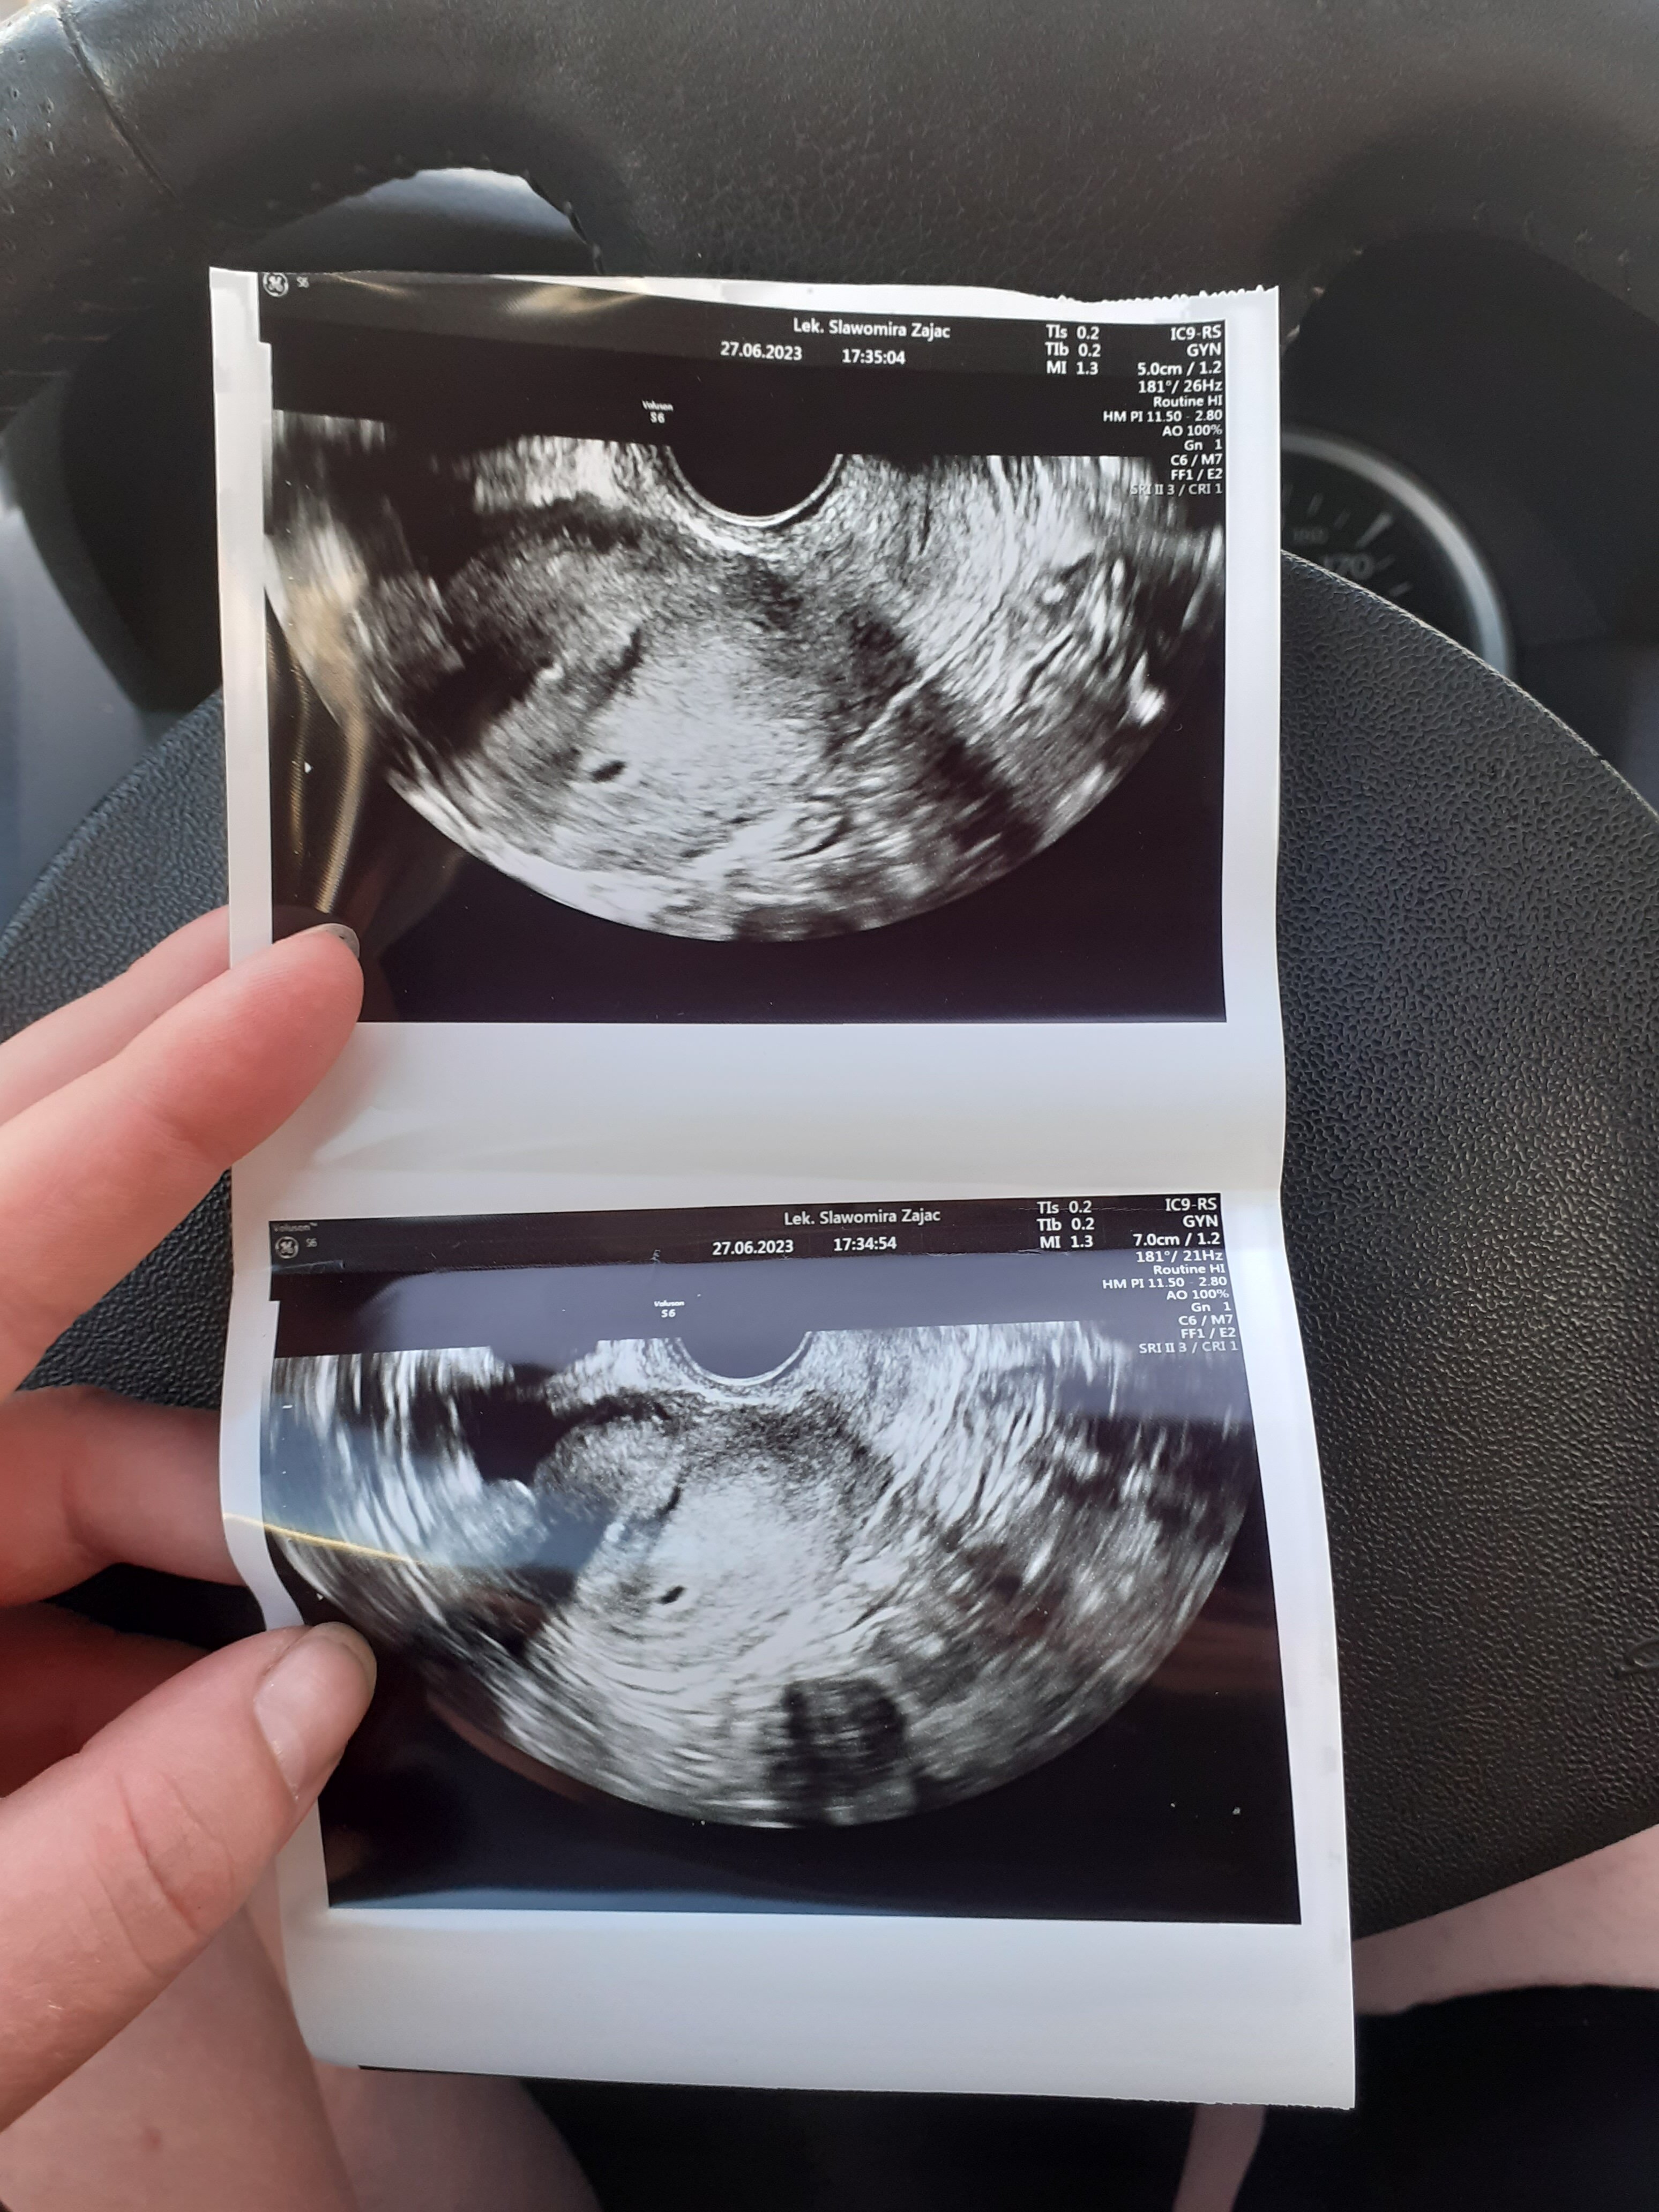

Ja tam widzę tylko jeden pęcherzyk.Witam. Mam pierwsze Usg to pierwsza ciąża. Zauważyłam na zdjęciu dwie "dziórki" ale pani ginekolog nic nie mówiła o ciąży bliźniaczej. Jak to było u was zrzucam zdjęcie z usg dodam że w rodzinie są bliźniacy i nie wiem co o tym myśleć

Na zdj 4 tydzieńNie widać nawet zarodka moim zdaniem na tym usg więc wydaje mi się że jest za wcześniej żeby oceniac czy to ciąża pojedyncza czy moga . Który Który tydzień, 5 ?